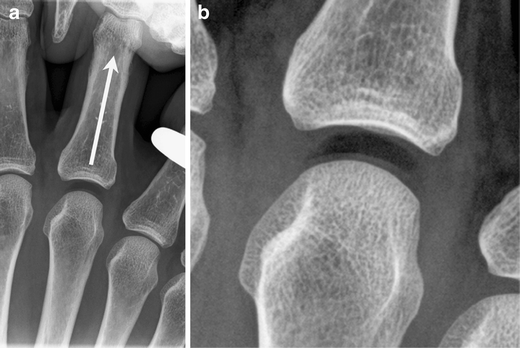

C 2003 by saunders an imprint of elsevier inc. Gas in the joint or pneumarthrosis in the context of trauma is not uncommon around superficial joints such as the knee and indicates that there is a penetrating wound with intra articular extension. Noomah tosis air or gas in an abnormal location in the body.

Pneumarthrosis. In the lungs emphysema involves enlargement of the distal airspaces and is a major feature of chronic obstructive pulmonary disease copd. Noomahr throsis gas or air in a joint. Intra articular gas or air pneumarthrosis can occur from a number of varied pathologies and should be interpreted according to the clinical context.

So far pneumarthrosis has proved of greater and more frequent benefit in the study of the knee than of any other joint. Pneumarthrosis information including symptoms causes diseases symptoms treatments and other medical and health issues. For want of more accurate information we have been compelled in the past to group many obscure lesions of the knee joint in the category of internal derangements.